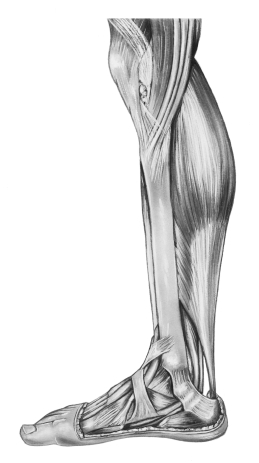

Тендинит – это воспаление ахиллова сухожилия, проявляющееся болью при нагрузке и даже в покое ( в запущенных случаях). Однако, исследования последних лет показывают, что при боли в ахилловом сухожилии возникают так называемые дегенеративные изменения (нарушения нормальной волоконной структуры сухожилия), не очень характерные для типичного воспаления. Поэтому все большее распространение получает более правильный термин тенопатия – т.е. заболевание сухожилия.

В основе тенопатии ахиллова сухожилия лежит его перенапряжение ( у бегунов, баскетболистов, волейболистов и других спортсменов, танцоров, акробатов, которые много прыгают, а также резко стартуют и останавливаются).

У здорового человека ахиллово сухожилие может удлиняться примерно на 5% от своей длины, что дает возможность сухожилию пружинить и выполнять функцию амортизатора. С возрастом способность сухожилия растягиваться снижается, поэтому чрезмерная нагрузка может привести к микроразрывам. К тенопатии ахиллова сухожилия может приводить плоскостопие, которое сопровождается гиперпронацией (т.е. заваливанием стопы внутрь), сухожилие перерастягивается и травмируется. Еще одна причина тенопатии ахиллова сухожилия – неудобная, неправильная спортивная обувь, что также может приводить к неправильному движению сухожилия и его микроразрывам.